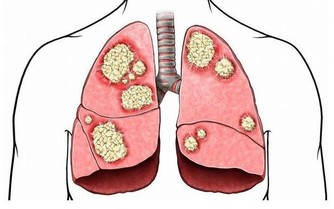

人們常說,是藥三分毒。這話一點沒錯。生活中很多常見藥都是可能造成肝損傷的,不宜長期服用。

阿司匹林、撲熱息痛,止痛藥等藥物均會引起中毒性肝損害。如果每天每天服用5克以上的阿司匹林,可能會引起急性肝損傷。

大部分抗生素類會造成肝臟的損傷,有一小部分的會造成肝炎的發生。並且速度極快,短期內爆發肝炎。

一些養胃藥、腸道疾病等藥物都會造成肝臟損傷,它們會造成體內轉氨酶升高,使用量大的話還會造成肝炎。

這些藥物都可以引起肝臟損傷。其中甲基多巴還可損害肝細胞和膽管。

可損傷肝臟。相反的,肝功能不好的人會改變格列齊特在體內的分佈,影響降糖效果,甚至會增加低血糖風險。

睾酮、甲地孕酮、甲地孕酮、雌三醇、丙泊酚等藥物可引起黃疸等肝損害。